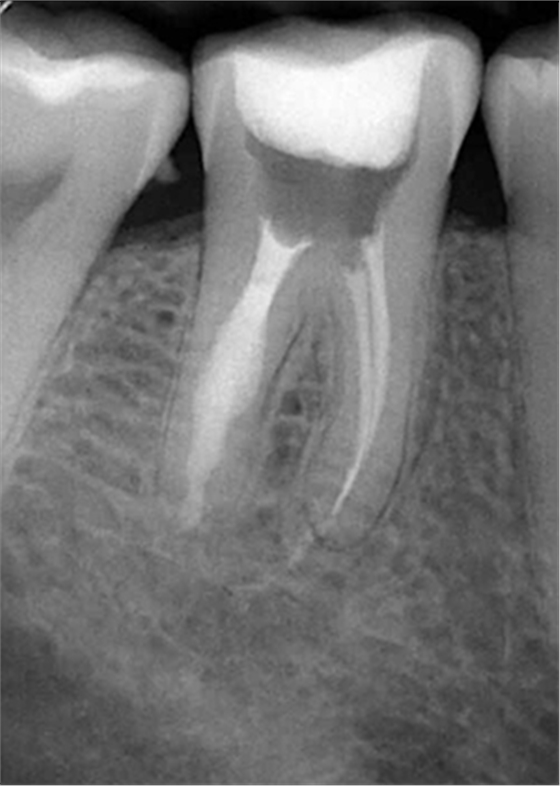

牙內(nèi)吸收通常無(wú)明顯癥狀。根據(jù)吸收的類型和原因,主要分為炎癥性吸收和替代性吸收。其中,炎癥性吸收可能繼發(fā)于前期牙本質(zhì)的細(xì)菌感染和創(chuàng)傷,牙本質(zhì)吸收過(guò)程的進(jìn)展不伴有吸收區(qū)鄰近部位硬組織的沉積,吸收部位可見(jiàn)大量肉芽組織,典型的影像學(xué)表現(xiàn)為,以根管為中心的橢圓形透光區(qū)。替代性吸收,導(dǎo)致根管內(nèi)牙本質(zhì)缺損的同時(shí),在缺損區(qū)某些部位還伴有骨樣組織的沉積,造成牙髓腔不規(guī)則的擴(kuò)大和根管連續(xù)性的破壞。根據(jù)牙內(nèi)吸收發(fā)生部位和嚴(yán)重程度的不同,又可呈現(xiàn)不同的征象。若吸收部位發(fā)展至牙冠,可以觀察到牙冠上出現(xiàn)粉紅色的點(diǎn),這是吸收細(xì)胞鄰近的結(jié)締組織高度血管化的結(jié)果。當(dāng)吸收部位位于根方,則可使得根管原有的形態(tài)缺失,X線片可見(jiàn)根管局部氣球樣的膨大,通常邊界清晰。若牙髓還有部分的活力,則患牙可能有慢性牙髓炎的表現(xiàn);若牙髓完全壞死,則可能發(fā)展成根尖周炎,而出現(xiàn)相應(yīng)的癥狀。竇道的出現(xiàn)往往是己發(fā)生慢性根尖膿腫或根管側(cè)穿的表現(xiàn)。由于患牙冠方的牙髓通常己經(jīng)壞死或被去除,因此敏感性測(cè)試常為陰性。